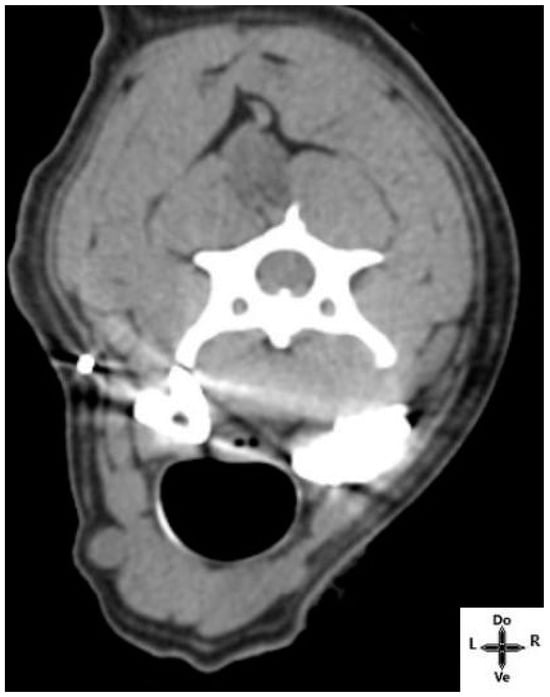

3.2.2. CT-Scan